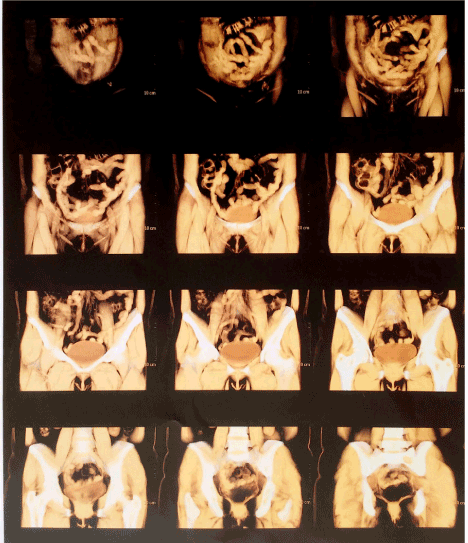

During the following queries, the patient complained experiencing depressive symptoms and agoraphobia. She reports that her physician observed the new imaging tests and noted that there was also no clinical significance. Considering the psychological symptoms comorbidities of migraine, the patient was prescribed paroxetine (50mg/day). However, the patient noticed continuity of psychological and physical symptoms. About a year using the same medication, the patient presented a discomfort followed by pain in the abdomen. In new neurological examination, abdominal MRI was performed and drug-induced hepatitis was observed (Figure 3).

Figure 3. Abdominal MRI with contrast showing drug-induced hepatitis